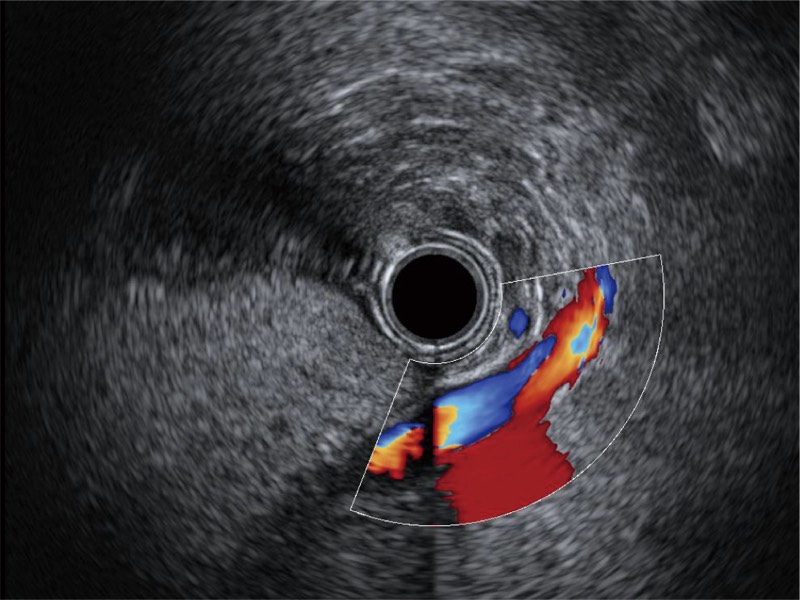

• 非线性融合造影

融合谐波技术

动态声压控制技术

TIC时间强度分析曲线

具有四种造影成像效果

• 清晰显示胆总管及周围血管分布